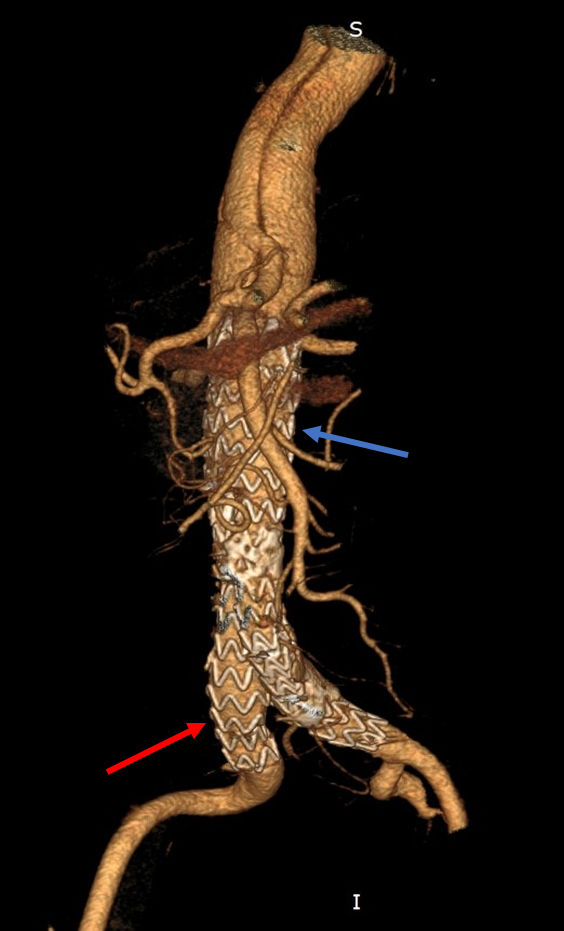

Fig. 4.Final result after stent-graft implantation. Stent-graft implanted in the abdominal aorta (blue arrow) and extensions into the iliac arteries (red arrow) with optimal position. Restoration of normal aortic flow and immediate isolation of the abdominal aortic aneurysm.